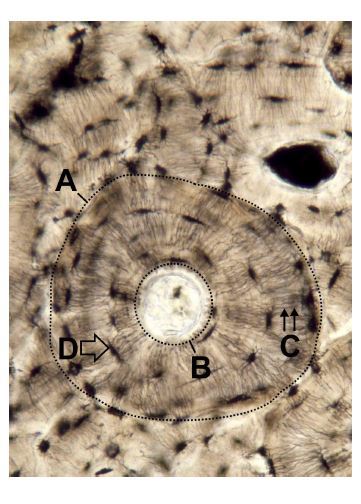

Ovenfor er vist et lysmikroskopisk billede af et væv.

a. Angiv navn for A-D.

a) A: Haversk system/Cortikalt osteon, B: Haversk kanal, C: Canaliculi, D: Lakune/osteocyt.

b) Det Haverske system er opstået ved aktivitet af osteoklaster, der har udhulet en tunnel med en diameter på typisk omkring 150 μm igennem allerede eksisterende knoglevæv. Efterfølgende har osteoblaster sat sig på tunnelens sider og har ved successive bølger af aktivitet deponeret osteoid, der efterfølgende mineraliseres. Dette giver ophav til en indadrettet knoglevækst med lagvis indfangning af osteoblaster i lakuner (som i D). Osteoblast aktivitet ophører og efterlader en Haversk kanal (som i B), der indeholder løst bindevæv, nerver og karforsyning.